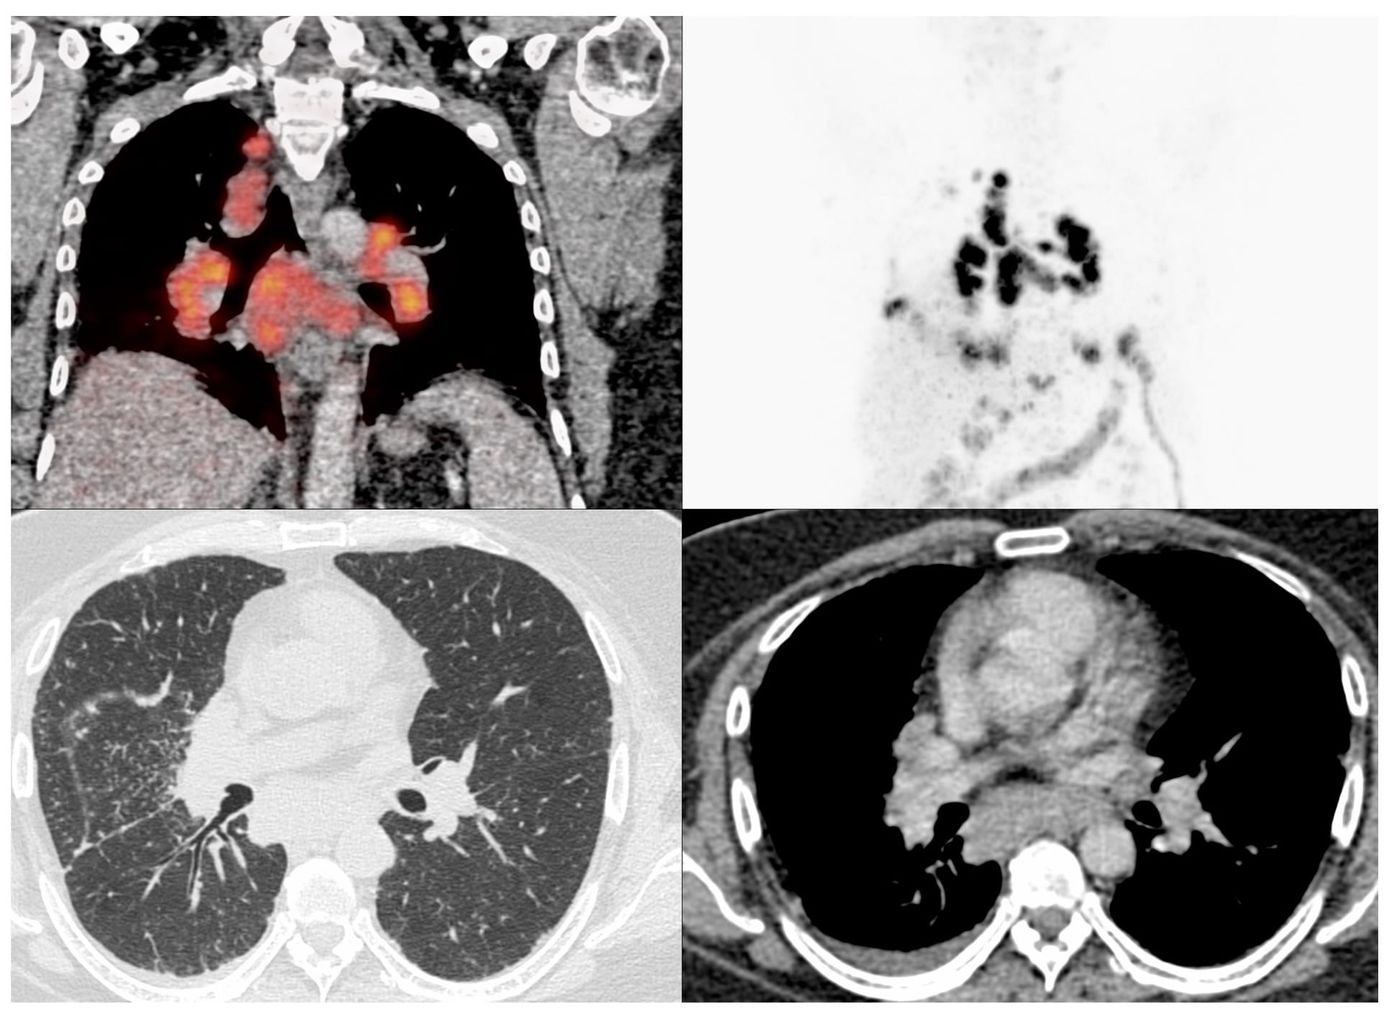

A discussion of the various patterns seen in CTDs. UIP and variants, NSIP, BIP, LIP, PPFE, OP, mixed and rapidly progressive.